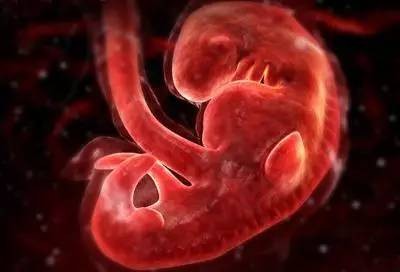

第一个月

胚胎正式开始发育啦,此时的胎儿像小海马一样,身长约几毫米。